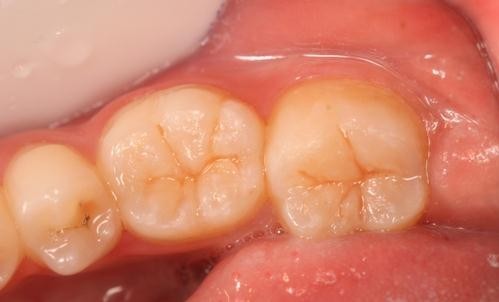

随访 讨论

效果很好,患者满意